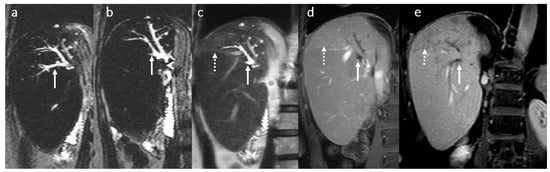

3.4. Biliary Anastomotic Stricture